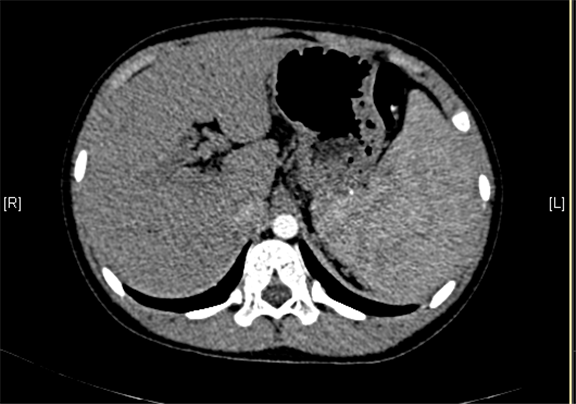

上腹部增强CT:门静脉主干走行迂曲、分支紊乱,考虑门静脉畸形可能性大,不除外门静脉海绵状变性。

术前CT检查:

平衡期